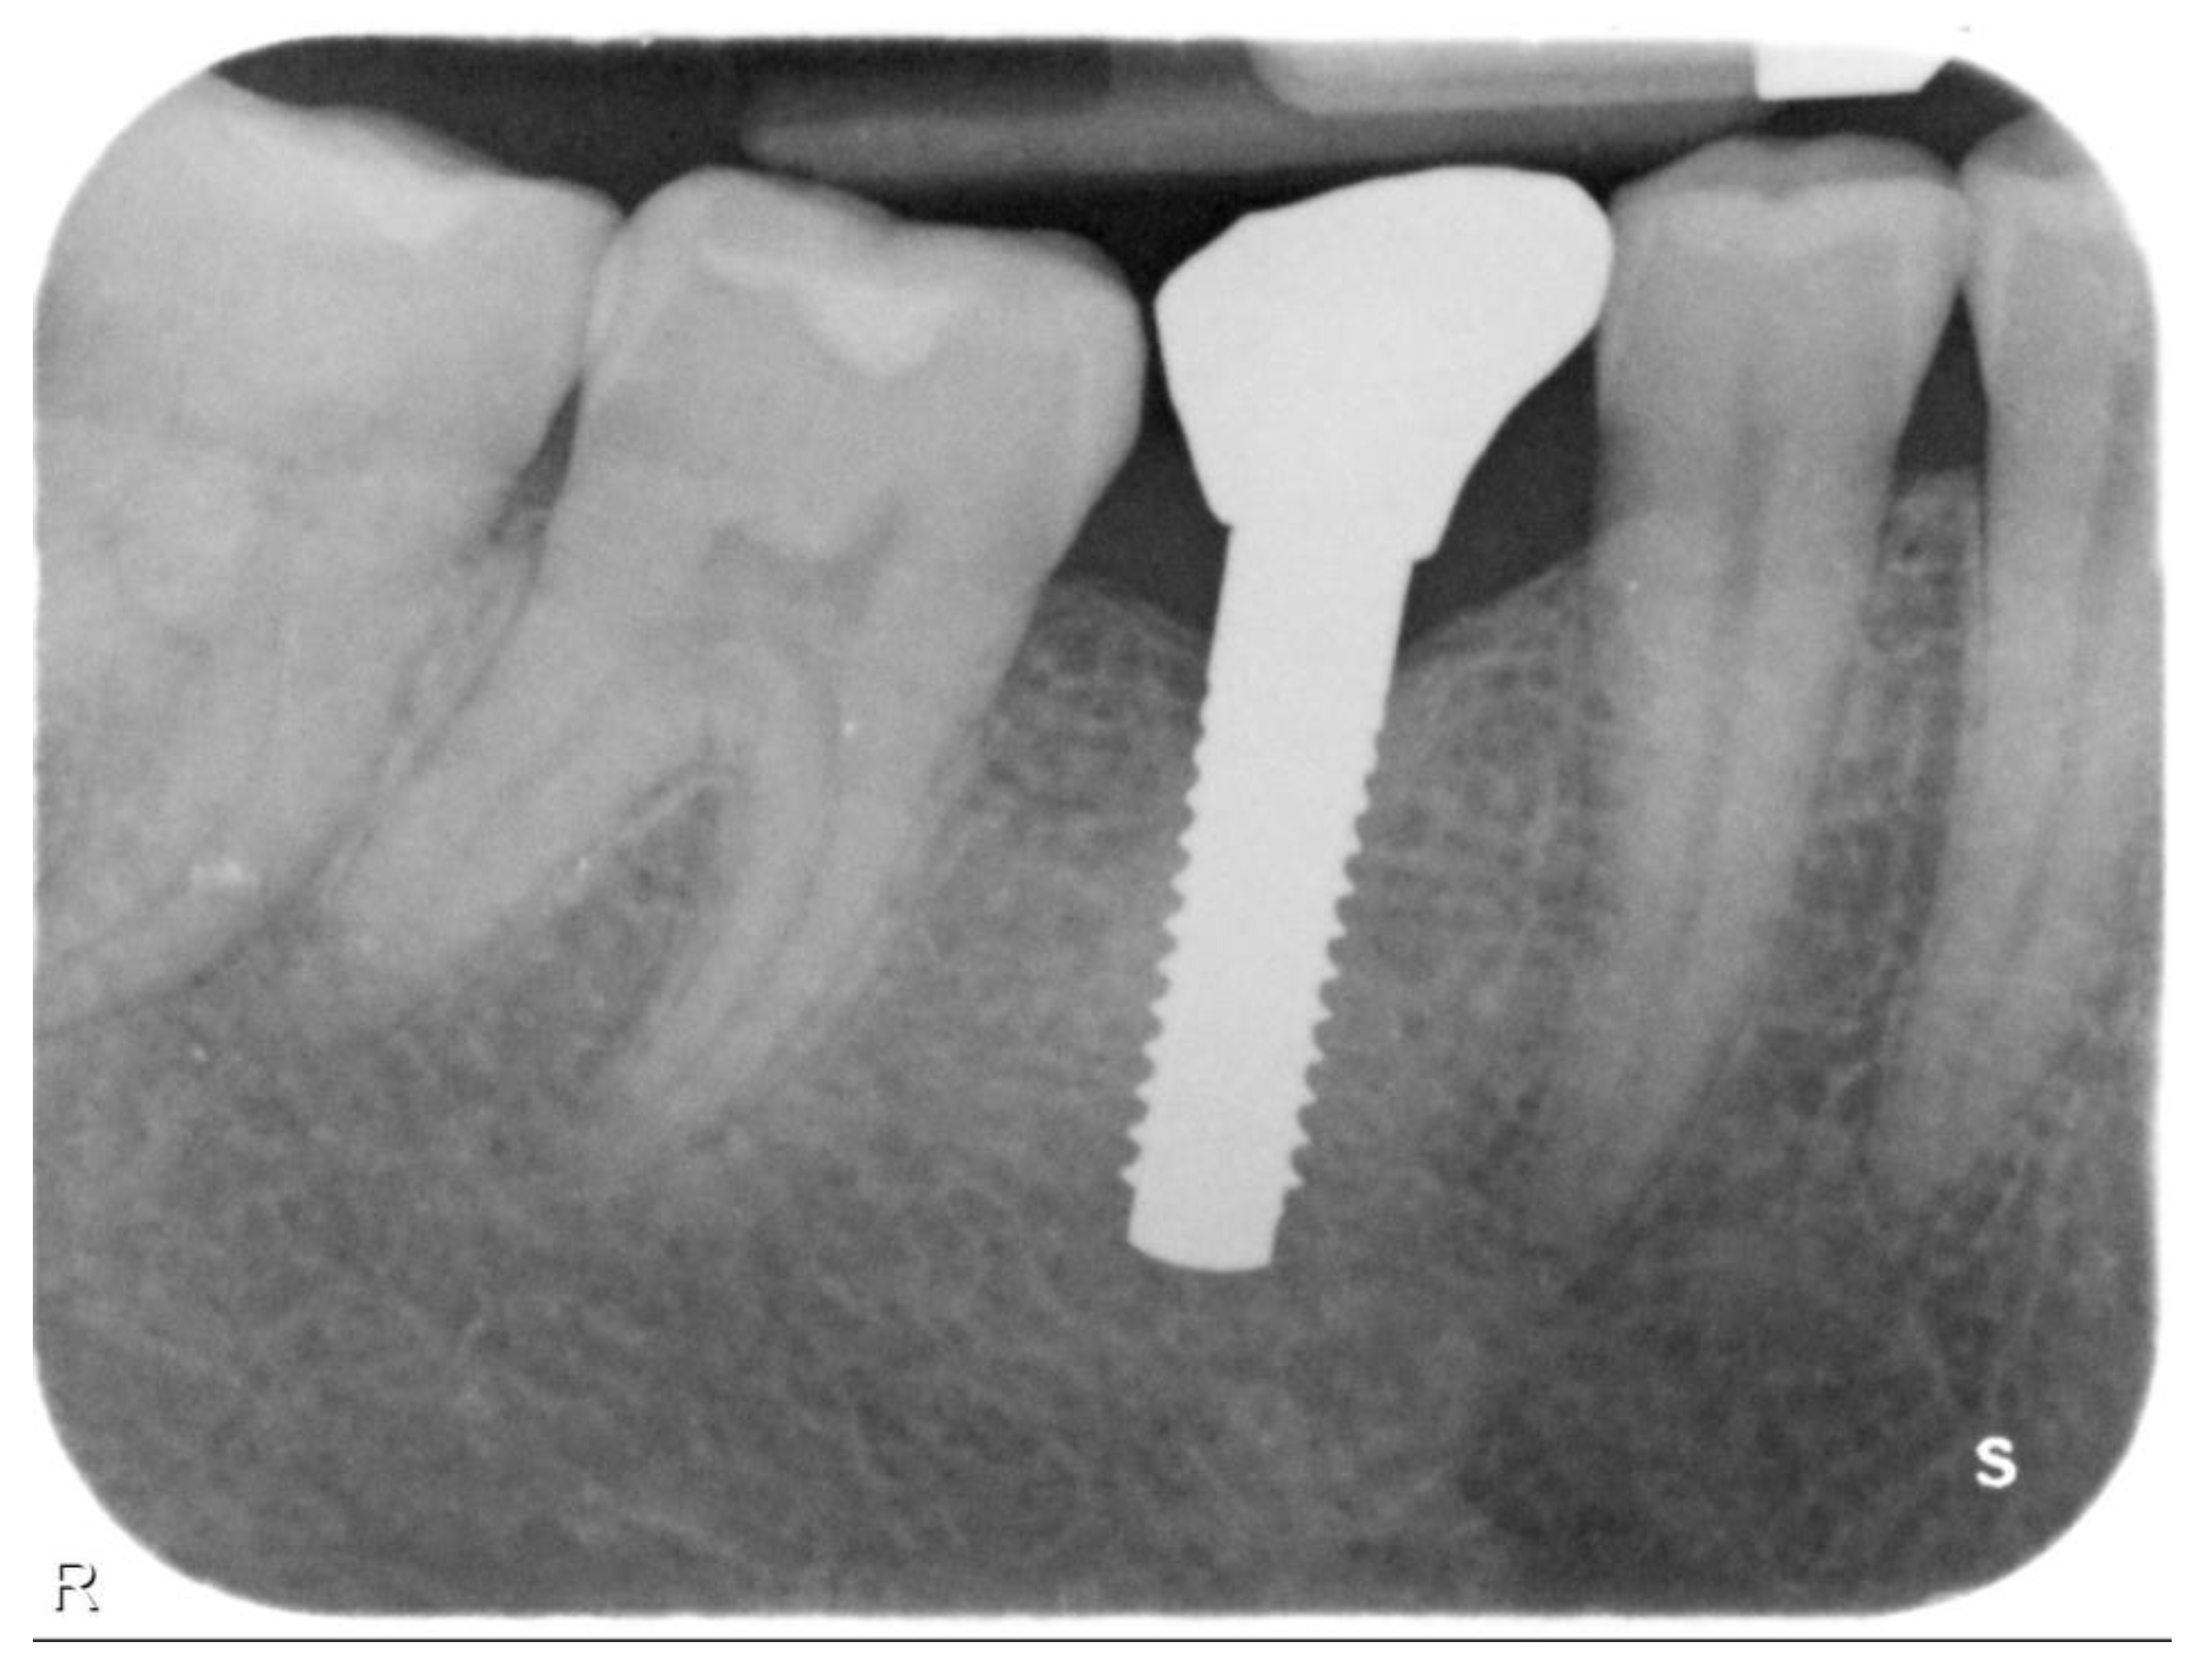

Single Crown Restorations Supported by One-Piece Zirconia Dental Implants: Case Series with a Mean Follow-Up of 58 Months

2. Materials and Methods

3. Results

| N | Follow-Up (Months) | Age | Gender | Implant Position | Implant Diameter (mm) | Implant Length (mm) | GBR | Placement Timing (IP/DP) | Loading Timing (IL/CL) | Mean MBL (mm) (T0–T1) |

|---|---|---|---|---|---|---|---|---|---|---|

| 1 | 96 | 42 | F | 11 | 4.1 | 12 | N | IP | IL | 1.9–3.48 |

| 2 | 96 | 59 | F | 21 | 4.1 | 14 | Y | IP | IL | 1.41–1.70 |

| 3 | 94 | 41 | M | 13 | 4.1 | 12 | N | IP | IL | 2.11–3.2 |

| 4 | 92 | 50 | M | 12 | 3.3 | 12 | N | DP | IL | 2.35–3.3 |

| 5 | 83 | 35 | M | 14 | 3.3 | 12 | N | DP | IL | 1.57–1.92 |

| 6 | 88 | 37 | F | 15 | 4.1 | 12 | N | IP | IL | 2.73–2.74 |

| 7 | 73 | 43 | F | 46 | 3.3 | 12 | N | DP | CL | 1.8–1.87 |

| 8 | 73 | 46 | F | 46 | 4.1 | 12 | N | DP | CL | 1.35–1.69 |

| 9 | 62 | 37 | F | 46 | 4.1 | 10 | N | DP | CL | 1.94–2.06 |

| 10 | 59 | 47 | M | 12 | 4.1 | 12 | Y | IP | CL | 0.36–2.03 |